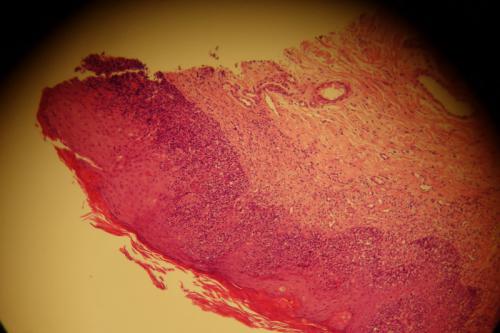

Cinq biopsies cutanées sont examinées selon différents niveaux de section et après réaction au PAS.

Sur deux biopsies, l’épiderme est hyperplasique, montre une couche granuleuse bien développée, une hyperkératose orthokératosique, coiffe un derme superficiel fibroblastique avec des foyers inflammatoires entourant les annexes notamment des glandes sudorales apocrines épitrichiales rétentionnelles, des follicules pileux parfois kystiques ou comédonneux. L’une de ces biopsies montre dans la couche cornée des résidus squamo-croûteux abondants, dans le derme on trouve des reliquats cicatriciels périannexiels.

Une autre biopsie montre un aspect un peu similaire avec un épiderme focalement sévèrement ulcéré, l’ulcération laissant à nu le derme sous-jacent qui est le siège d’un tissu de granulation néovascularisé et d’un infiltrat inflammatoire à forte prédominance plasmocytaire. Dans l’épiderme adjacent, on observe quelques petits foyers d’exocytose basale de cellules mononucléées lymphocytaires mais sans nettes atypies.

Sur deux autres biopsies, une d’entre elles a des annexes bien développées et un tissu musculaire strié bien visible (il pourrait s’agir pour l’une d’entre elles de la biopsie à localisation faciale). On observe sur ces biopsies, un aspect différent. L’épiderme est le siège d’une acanthose irrégulière d’intensité modérée et d’une hyperkératose parakératosique. Dans les couches les plus basales de l’épiderme, on observe un intense infiltrat cellulaire formé principalement de cellules mononucléées.

Photo 13 : infiltrat lymphoïde épidermotrope

Il s’agit d’une exocytose de cellules individuelles qui ont tendance toutefois à se collecter en petits micro-abcès. Ces cellules sont mononucléées, dotées d’un noyau plicaturé à chromatine pâle, à nucléolation discrète mais parfois multiple et faiblement apparente et à cytoplasme pâle peu abondant, polaire. Un certain nombre de ces cellules montre une Photo mitotique. Elles ont une taille et une forme variables. L’infiltrat occupe les deux tiers profonds de l’épaisseur épidermique. A la jonction entre l’épiderme sain et cet épiderme infiltré, on observe un grand nombre de cellules acidophiles plus ou moins rétractées, aux noyaux viables ou rétractés évoquant des corps apoptotiques. Un certain nombre d’entre eux sont entourés de quelques cellules mononucléées lymphocytaires satellites. Dans le derme, on trouve une vascularisation, une fibroplasie et un infiltrat qui reste périvasculaire et polymorphe. On observe également autour des annexes des manchons inflammatoires mais plutôt plasmocytaires avec une exocytose seulement très ponctuelle au sein de certaines annexes, sans jamais former une exocytose aussi massive que celle de l’épiderme.

Conclusion

L’aspect histologique est assez déroutant : sur deux biopsies, on observe surtout des lésions de dermatite chronique cicatricielle avec des lésions anciennes ou séquellaires de pyodermite profonde, l’une des biopsies étant ulcérée. Une biopsie montre un aspect intermédiaire et deux autres biopsies montrent une forte exocytose basale strictement intra-épidermique de cellules lymphoïdes atypiques associée à de nettes lésions de nécrose kératinocytaire et parfois de satellitose.